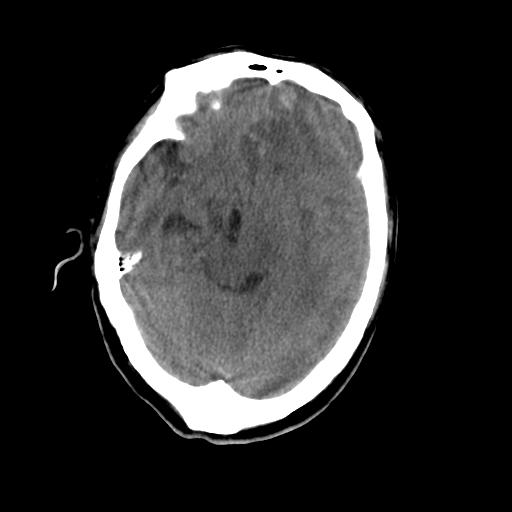

男,78岁。自诉两周前因右侧肢体障碍行ct检查,诊断为脑梗塞(患者ct片已丢失)治疗好转后出院。现因意不清12小时,又行ct检查。

结合病史考虑左侧额颞顶叶出血性脑梗塞。

结合病史考虑左侧额颞顶叶出血性脑梗塞